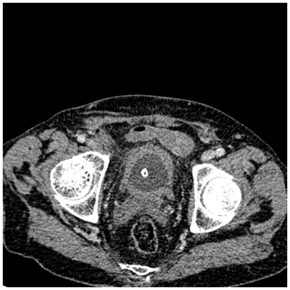

Recto-sigmoidoscopy failed to find the orifice of the fistula. Abdominopelvic computed tomography showed a circumferential thickening of the bladder wall with a posterior parietal collection of 11*16 mm in contact with the sigmoid colon. Uncomplicated colonic diverticula were also revealed (Figure 3−5).

Figure 4 Transversal computed tomography scan showing circumferential bladder wall thickening because of urinary obstruction.